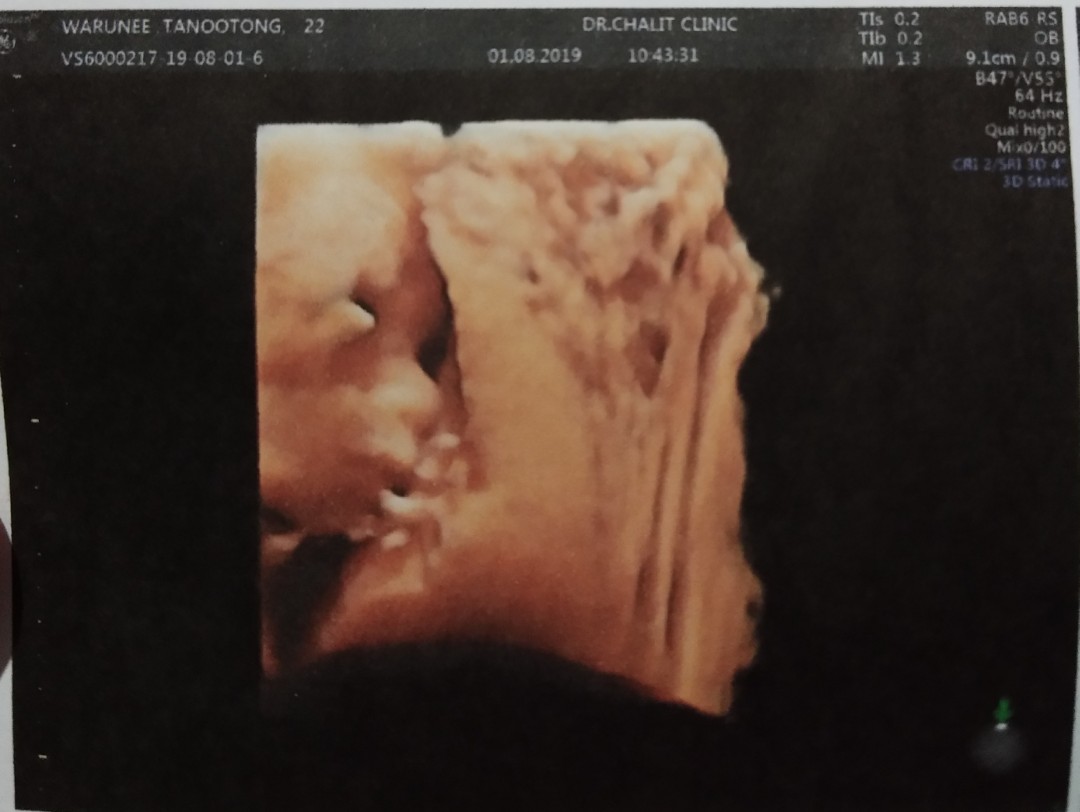

ซาว22wชัดมากค่ะ